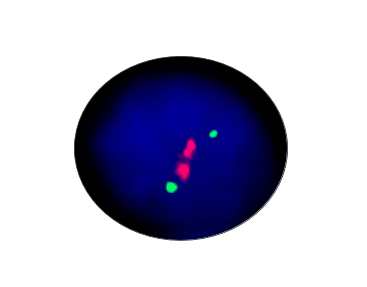

MYCN Amplification

Probe Description: MYCN/Cep 2